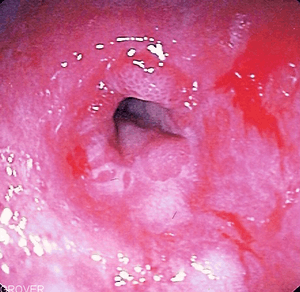

Endoscopic image of peptic stricture, or narrowing of the esophagus near the junction with the stomach due to chronic gastroesophageal reflux. This is the most common cause of dysphagia, or difficulty swallowing, in scleroderma.

Diffuse scleroderma can affect any part of the gastrointestinal tract.[8] The most common manifestation in the esophagus is reflux esophagitis, which may be complicated by peptic stricturing, or benign narrowing of the esophagus.[9] This is best initially treated with proton pump inhibitors for acid suppression,[10] but may require bougie dilatation in the case of stricture.[8]

Scleroderma can decrease motility anywhere in the gastrointestinal tract.[8] The most common source of decreased motility is the esophagus and the lower esophageal sphincter, leading to dysphagia and chest pain. As scleroderma progresses, esophageal involvement from abnormalities in decreased motility may worsen due to progressive fibrosis (scarring). If this is left untreated, acid from the stomach can back up into the esophagus, causing esophagitis and GERD. Further scarring from acid damage to the lower esophagus many times leads to the development of fibrotic narrowing, also known as strictures which can be treated by dilatation, and Barrett's esophagus.